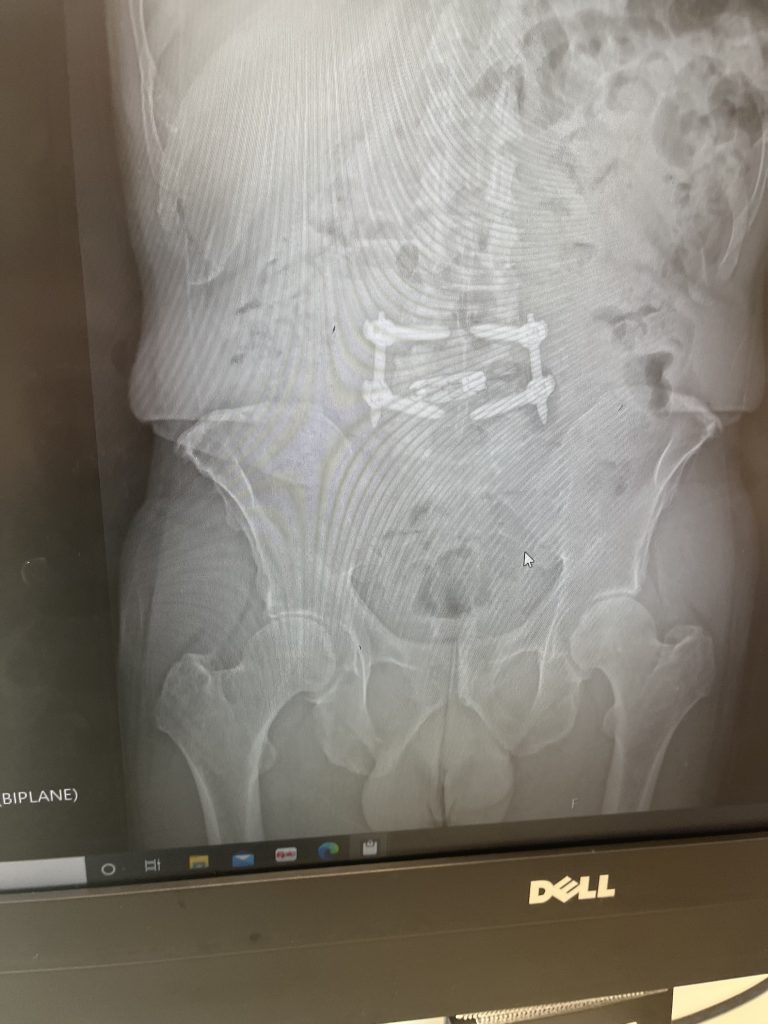

I went to HSS to hear a fifth opinion. I wanted to avoid surgery. I used to walk, run, swim and ride my bicycle, but my discomfort and pain didn't allow me to do exercise. When I met Dr. Qureshi and his great assistants and told me I needed to operate, I had no doubt I had to have the surgery done by Dr. Qureshi. I went to surgery after 2 days. At the beginning, I had a little discomfort but I could walk. During the first 8 weeks, I had discomfort, but was feeling better than before. Every time I would email Dr. Qureshi and his assistants, I would get a response in less than 30 minutes. Dr. Qureshi suggested I get a hip injection and that really was a game changer. My life is back to normal. My back is 100% and my hip 75%. I suggest to whoever has back pain or discomfort not to suffer. Thank you Dr. Qureshi and team!